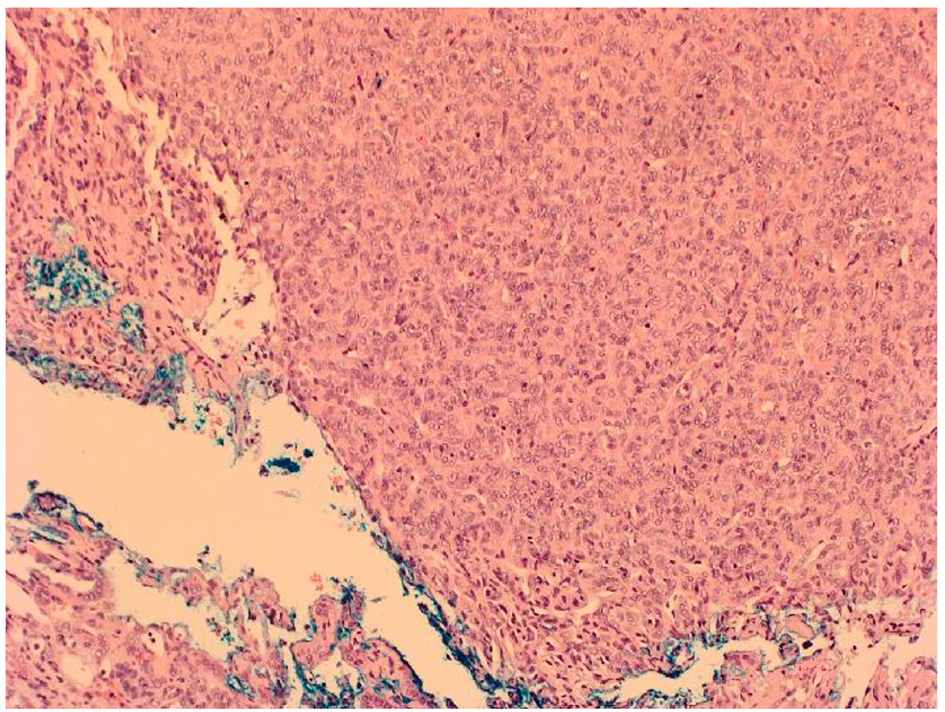

![]() Click for large image | Figure 2. Microscopic appearance of HPC showing densely packed population of spindle or oval shaped cells with elongated nuclei separated by slit-like vascular spaces. |

The development of metastases from a primary brain tumor is even rarer. Our case developed from a primary brain HPC which tends to be unilateral only [9]. HPCs originate from pericytes that surround capillaries and regulate blood flow and permeability. They can therefore develop from a multitude of sites around the body, including the kidney, but predominantly originate from the extremities, head and neck, pelvis and extremities [10]. Stout and Murray in 1942 became the first authors to define HPC as a distinct vascular neoplasm whilst renal HPCs were first noted by Black and Heinemann several years later [11, 12]. They are highly vascularized soft tissue tumors surrounded by a capsule or pseudocapsule often with high rapid growth and malignant potential. Microscopically, the tumor comprises of a densely packed population of spindle or oval shaped cells with elongated nuclei, often separated by slit-like vascular spaces (Fig. 2). The cells lack pleomorphism or hyperchromasia and have positive immunostaining for CD34 and vimentin.